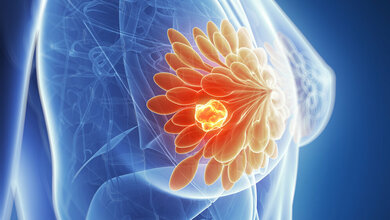

Bösartige Tumoren verbrauchen Nährstoffe und Sauerstoff schneller als gesunde Zellen. Dazu nutzen sie die Blutgefäße in ihrer Umgebung. Je nach Tumorart und genetischem Profil gibt es Unterschiede im inneren Erscheinungsbild von Tumoren. In aller Regel weisen Tumoren über ihr Volumen hinweg unterschiedliche Muster auf. Die Rolle dieser räumlichen Heterogenität ist bisher weder ausreichend verstanden noch an lebenden Tumoren untersucht worden. Heute übliche Verfahren wie die optische Mikroskopie, die zum besseren Verständnis biologischer Funktionen in Tumoren eingesetzt werden, ermöglichen nur begrenzte Erkenntnisse über die räumliche Heterogenität von Tumoren. Sie greifen lediglich auf Gewebemengen von weniger als einem Kubikmillimeter zu.

So können Forscherinnen und Forscher auf Bildern von Mammakarzinomen bei Mäusen Muster erkennen, die auf das Vorhandensein oder Fehlen von Blutgefäßen hindeuten – und so die Muster der Blutversorgung untersuchen. MSOM kann auch den Hämoglobinspiegel abbilden und anzeigen, ob Sauerstoff an den roten Blutfarbstoff gebunden ist oder nicht. Darüber hinaus wurden MSOM-Bilder bereits verwendet, um die Durchlässigkeit von Gefäßwänden für Nanopartikel zu bestimmen. Am Mausmodell konnten die Wissenschaftlerinnen und Wissenschaftler bereits nachverfolgen, wie winzige Goldpartikel transportiert wurden.